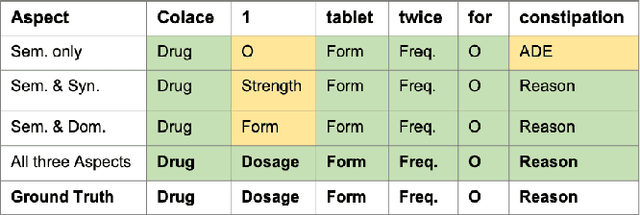

Extracting meaningful drug-related information chunks, such as adverse drug events (ADE), is crucial for preventing morbidity and saving many lives. Most ADEs are reported via an unstructured conversation with the medical context, so applying a general entity recognition approach is not sufficient enough. In this paper, we propose a new multi-aspect cross-integration framework for drug entity/event detection by capturing and aligning different context/language/knowledge properties from drug-related documents. We first construct multi-aspect encoders to describe semantic, syntactic, and medical document contextual information by conducting those slot tagging tasks, main drug entity/event detection, part-of-speech tagging, and general medical named entity recognition. Then, each encoder conducts cross-integration with other contextual information in three ways: the key-value cross, attention cross, and feedforward cross, so the multi-encoders are integrated in depth. Our model outperforms all SOTA on two widely used tasks, flat entity detection and discontinuous event extraction.